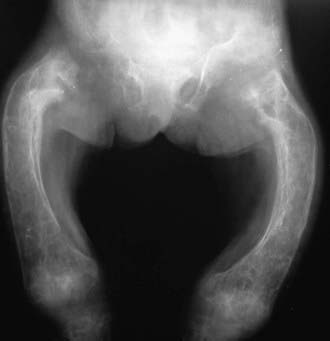

Hyperphosphatasia is characterized by excessive elevation of the bone isoenzyme of alkaline phosphatase in serum and significant growth failure. Osteoid proliferation in the subperiosteal portion of bone results in separation of the periosteum from the bone cortex. Bowing and thickening of the diaphyses are common, along with osteopenia (see Fig. 697-1 on the Nelson Textbook of Pediatrics website at www.expertconsult.com image). The disease usually has its onset by 2-3 yr of age, when painful deformity developing in the extremities leads to abnormal gait and sometimes fractures. Other common findings include pectus carinatum, kyphoscoliosis, and rib fraying. The skull is large, and the cranium is thickened (widened diploë) and may be deformed. Skull involvement can lead to progressive and profound hearing loss. Radiographically, the bony texture is variable; dense areas (showing a teased cotton-wool appearance) are interspersed with radiolucent areas and general demineralization. Long bones appear cylindrical, lose metaphyseal modeling, and contain pseudocysts that show a dense, bony halo.

Figure 697-1 Hyperphosphatasia showing bowing and thickening of the diaphyses and osteopenia.

(From Slovis TL, editor: Caffey’s pediatric diagnostic imaging, ed 11, vol 2, Philadelphia, 2008, Mosby.)